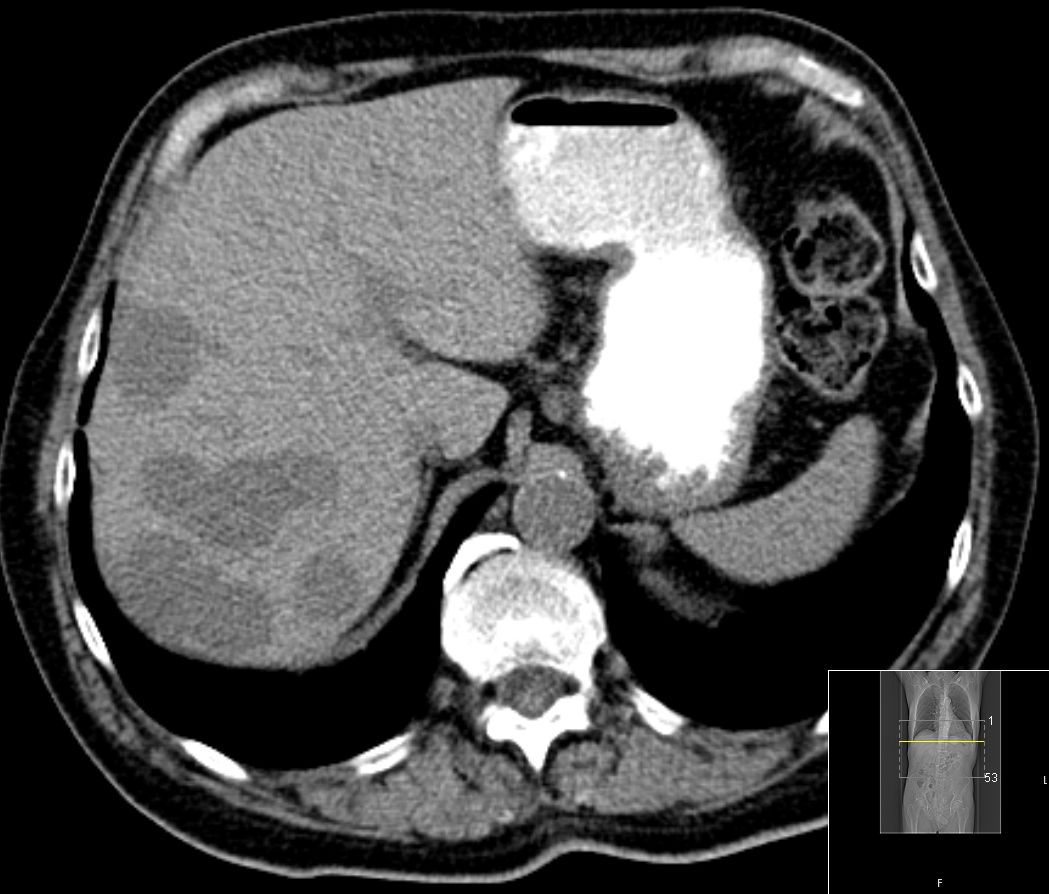

In der portalvenösen Phase Metastasen gut

abgrenzbar.![]() |